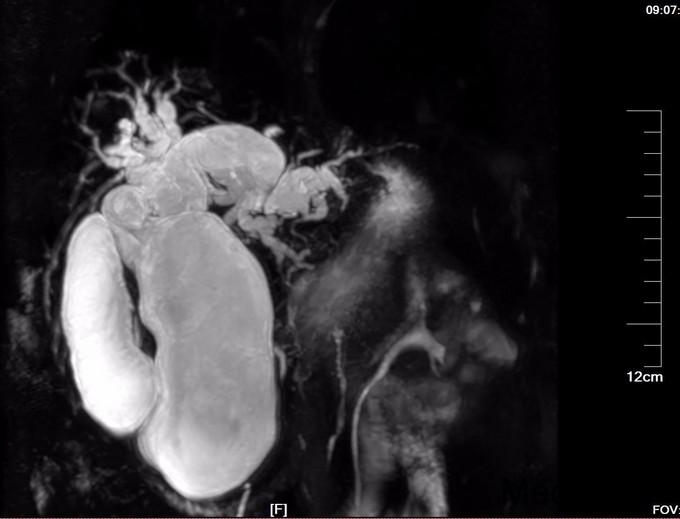

查体:腹部略膨隆,未见胃肠型及蠕动波,未见腹壁曲张静脉,右上腹部压痛阳性,无反跳痛或肌紧张,未及包块,肝脾肋下未及,Murphy氏征阳性,肝区扣痛阳性,肾区无扣痛,肠鸣音减弱,约4次/分,未闻及气过水声。 辅查: MR平扫+增强:肝脏大小形态未见异常,各叶比例正常,未见异常信号灶。肝内胆管、胆囊管及胆总管多发囊状扩张,胆总管直径6cm左右,壁厚且明显强化,腔内点状T2WI低信号影。胆囊饱满,其内可见聚集点状低信号影,胆囊壁增厚且明显强化。门脉血管显示清楚,走行正常。胰腺形态信号未见异常,胰管未见扩张。脾脏不大。增强扫描未见异常强化病灶。 MRCP:胆囊体积增大,肝内胆管、胆囊管及胆总管多发囊状扩张。胰管显影,形态走行未见异常。 CT 胆总管囊状扩张,囊壁较厚,前壁见点状钙化,较宽处直径约6.7cm,胆总管末端壁增厚,管腔狭窄;增强扫描扩张胆总管壁明显强化。肝内胆管扩张,胆囊增大,胆囊壁增厚、强化尚均匀,囊内未见异常密度影。 肝内未见异常密度影。胰腺形态、密度未见异常。脾不大。腹膜后未见确切肿大淋巴结影。